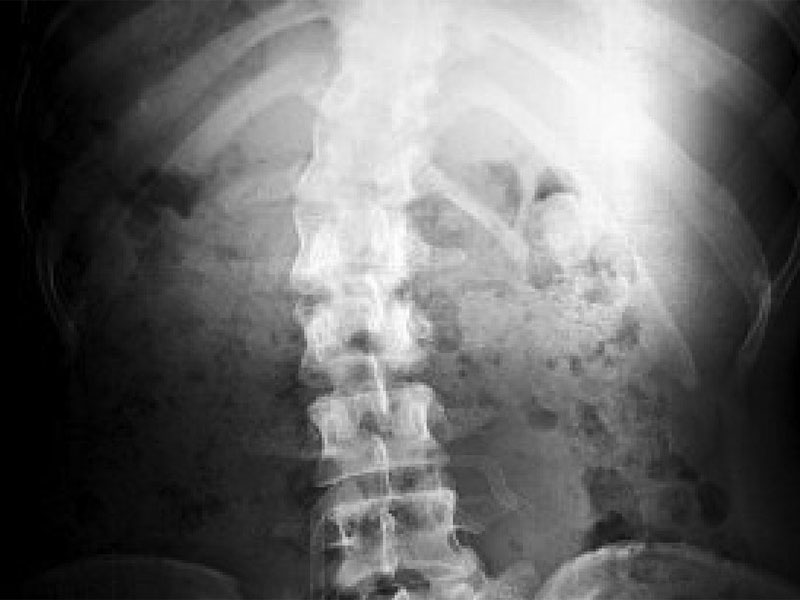

Diagnostica per immagini

La radiografia è lo strumento fondamentale per diagnosticare l’osteonecrosi disbarica, ma dipende dalla qualità della radiografia e dall’esperienza del radiologo. Sebbene possano essere affette solo anche e spalle, è necessario avere radiografie anche della parte bassa del femore e di quella alta della tibia per identificare tutte le possibili lesioni ossee.

Anche se indicata per la diagnosi, la radiografia non è indicata per monitorare le variazioni nel tempo di tale malattia. Altre metodiche indicate per la diagnosi includono la scansione con MDP (99mTechnetium Methyl-dipolyphosphate), molto sensibile nel rilevare una patologia ossea localmente. Una zona scura indica aumentate perfusione e metabolismo, riconoscibile anche solo poche ore dopo l’immersione. Una positività della scansione non è diagnostica e richiede un controllo radiologico a distanza.

La risonanza magnetica (Magnetic resonance imaging – MRI) (Fig.4) riesce ad individuare precocemente le lesioni, ma costosa generalmente non rientra tra gli esami di screening per una ampia popolazione. Fu usata nel 1981 dal Decompression Sickness Registry, il quale ha rilevato che la percentuale di necrosi, sia articolare che ossea, aumenta in un campione di subacquei con l’età e con l’esperienza.

E’ stata trovata almeno una lesione nel 4,2% di una popolazione di 4980 subacquei.

Non sono state trovate lesioni nei subacquei che non hanno mai oltrepassato i 30 metri di profondità, ma sono state trovate in 30 su 190 maschi (15,8%) che si erano immersi a profondità superiori ai 200metri.

Da ciò si può supporre che esaminare dei subacquei “profondisti”con MRI può aiutare a diagnosticare lesioni articolari e a prevenirne il collasso. ( 9)